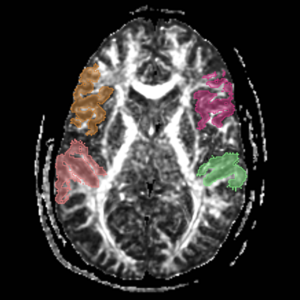

Boundaries for the ROI's, mainly using FA maps & color by orientation, followed by the color coding of the labelmaps.

IC - Internal CapsuleROI 1) find anterior commisure on axial view and draw ROI on coronal slice on each side on midsag line Top boundary for ROI 1: Caudate/putamen line Bottom boundary for ROI 1: draw entire plane of AC; IC is only superior to AC line. ROI 2) go to the anterior most point of the corpus collosum according to saggital view. Draw ROI so it covers entire (left or right) hemisphere of brain on the perpendicular Coronal Slice.

Arcuate FasciculusThese labelmaps ('caseD00XXX-FS-arcuate-final.nhdr') were created using automatic gray matter parcellation in Freesurfer and coregistered in Slicer to corresponding DTI dataset. The labelmaps were dilated in Slicer to increase coverage of gray matter.